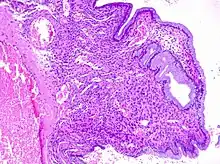

Diagnosis

Cervical polyps can be seen during a pelvic examination as cherry-red or greyish-white projections from the cervical canal.[2] Diagnosis can be confirmed by a cervical biopsy which will reveal the nature of the cells present.[4]

The cause is not known.[1] Risk factors include multiple prior births or sexually transmitted infections.[2] They tend to occur as single growth and are less than a centimeter in size; though may rarely be much larger.[1][2] Their color may vary from grey to red.[2] Most are not serious; thought, 0.2% to 1.5% are precancerous or cancerous, which mostly occur after menopause.[2] Diagnosis is generally suspected based on speculum examination and confirmed by histological examination.[2]